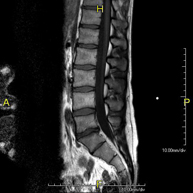

- Lumbar spine MRI

This non-invasive diagnostic procedure uses an electromagnetic field and radio waves (from a transmitter and receiver) to acquire high-definition anatomical images of the lumbar and sacral regions. It is a radiation-free procedure. Indicated for: trauma, sciatica, herniated discs, tumours, infections.